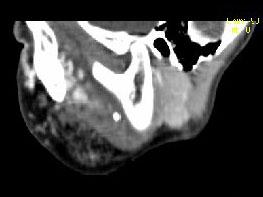

问题 男,12岁,左面颊肿大5年余,局部呈紫红色,CT如图所示,最可能诊断为()

选项 A.蔓状血管瘤 B.血管外皮瘤 C.动静脉畸形 D.慢性腮腺炎 E.下颌下腺慢性炎症

答案 A